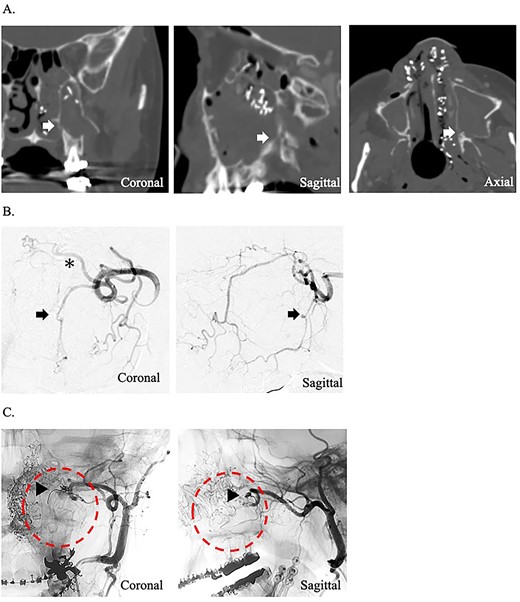

A 24-year-old man presented to our department with massive epistaxis from the left nose. The patient underwent Le Fort I maxillary osteotomy and sagittal split ramus osteotomy for jaw deformity 10 days earlier by the dentist at another hospital and had repeated epistaxis episodes after hospital discharge. After the patient came to our hospital, the left nasal cavity was examined endoscopically; however, the hemorrhage had stopped, and no definite bleeding points were identified. Contrast-enhanced computed tomography of the paranasal area revealed that the maxilla and pterygoid fragment were cut and separated. In addition, a cut of the bone was found around the descending palatine artery, as in case 1 (Fig. 2A). The preoperative hemoglobin concentration was 14.2 g/dL, and the hematocrit was 40.0%. After hemorrhage, the hemoglobin concentration (11.3 g/dL) and hematocrit (32.4%) decreased. After hospitalization, massive hemorrhage recurred, and hemostasis was impossible by endoscopy. Therefore, angiographic embolization by a radiologist was selected. The angiography revealed vascular injury to the left descending palatine artery, and embolization was performed by gelatin sponges (Fig. 2B and C). As in case 1, hemostasis was sufficiently complete; however, after angiographic embolization, the hemoglobin concentration and hematocrit severely decreased to 9.3 g/dL and 27.5%, respectively.

(A) Postoperative coronal, sagittal, and axial computed tomography images, which show the separated bone parts of the left maxilla (arrow). (B) Coronal and sagittal selective angiographic images from the left internal maxillary artery. The arrows indicate the suspected region of injury to the left descending palatine artery. The asterisk indicated the left sphenopalatine artery. (C) After embolization and coronal and sagittal selective angiographic images. The circle indicated the disappearance of the vascular flow area.